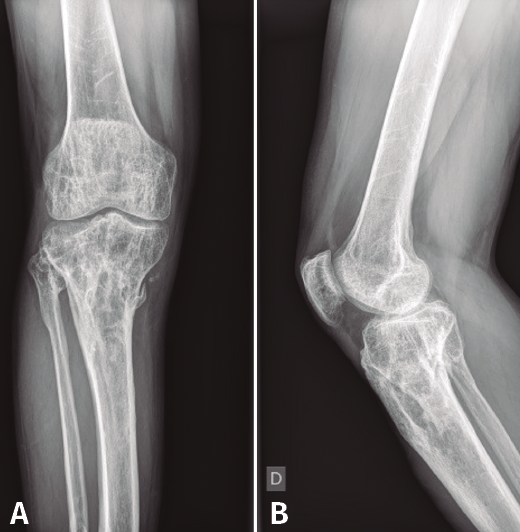

Figura 8. Radiografías del extremo proximal de la tibia donde se objetiva la correcta incorporación del injerto aportado.

Al cabo de 4 meses y tras la resolución del proceso séptico, se procede al relleno de la cavidad con injerto autólogo de cresta iliaca, cuya evolución fue hacia la incorporación de este (Figura 8).